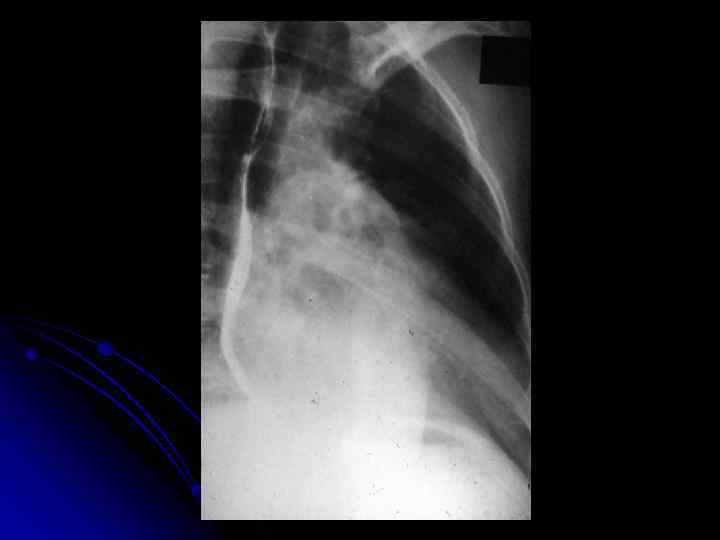

Рентгенограмма грудной клетки больного со стенозом трехстворчатого клапана во второй косой проекции.